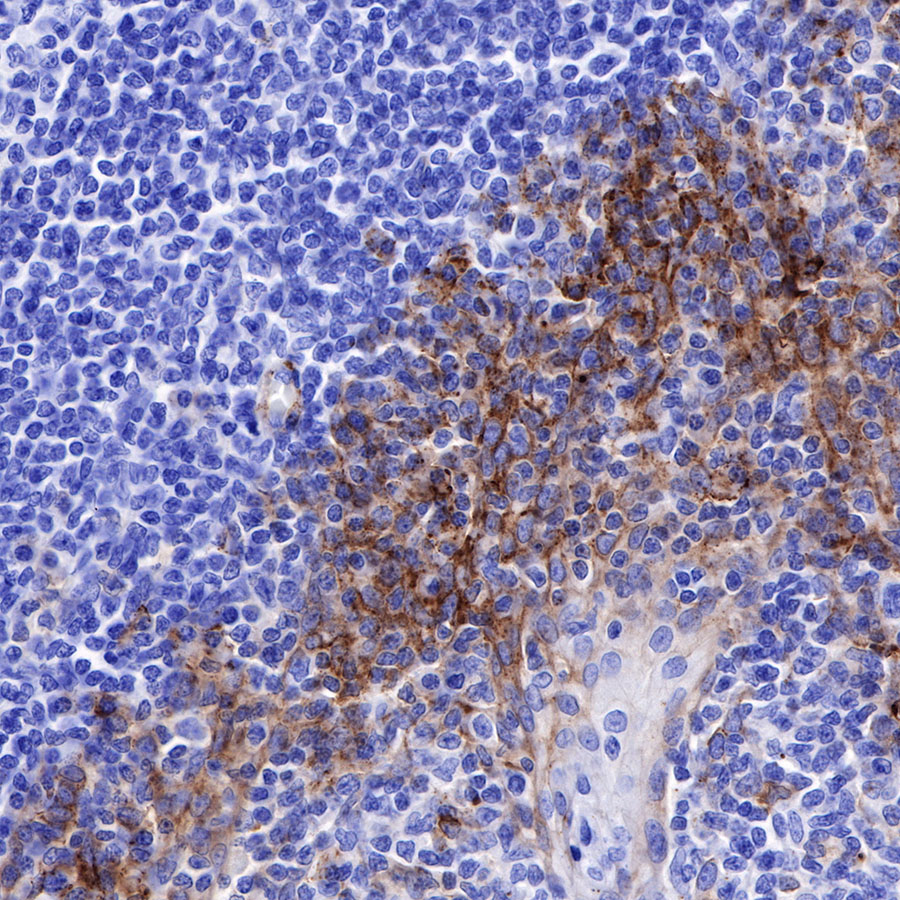

Syndecan-1 (CD138) is mostly restricted to epithelia, and bears heparan sulfate chains that are capable of interacting with a large array of polypeptides, including extracellular matrix components and potent mediators of proliferation, adhesion and migration. For this reason, it has been studied extensively with respect to carcinomas and tumor progression. Frequently, but not always, syndecan-1 levels decrease as tumor grade, stage and invasiveness and dedifferentiation increase. However, in some tumors, levels of syndecan-1 increase, but the characterization of its distribution is relevant. There can be loss of membrane staining, but acquisition of cytoplasmic and/or nuclear staining that is abnormal. Moreover, the appearance of syndecan-1 in the tumor stroma, either associated with its cellular component or the collagenous matrix, is nearly always a sign of poor prognosis [PMID: 33921767].

Immunohistochemistry